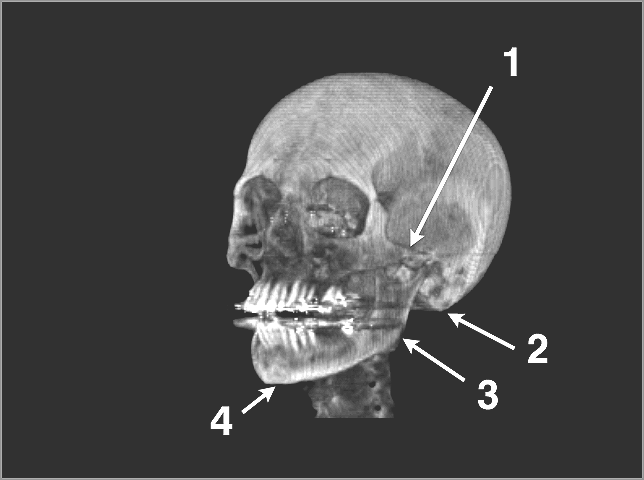

Structures to Know

Identifications